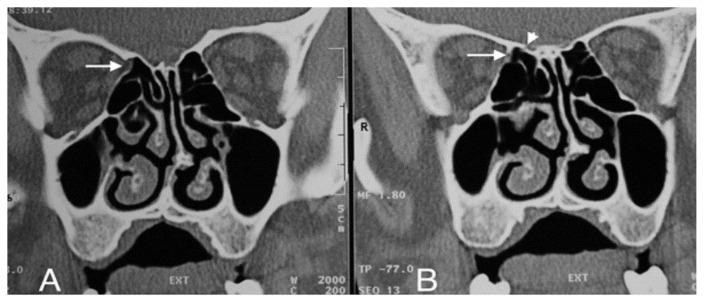

BACKGROUND/AIM: The aims of this study are to determine the incidence and more frequent localizations of orbital fat tissue herniation accompanying dehiscences in the medial orbital wall and to investigate the relationship between orbital fat tissue herniations and the anterior and posterior ethmoidal foramina.

One thousand two hundred patients who had undergone computed tomography with a preliminary diagnosis of sinusitis and who had no previous facial, orbital, paranasal sinus surgeries or history of trauma were retrospectively analyzed. The localization of the ethmoidal foramina and orbital fat tissue herniations were marked. In patients with orbital fat tissue herniation, the relationship between the localization of orbital fat tissue herniation and the anterior and posterior ethmoidal foramina was investigated.

The incidence of orbital adipose tissue herniation in our study was 7.9%. Of the 98 herniations on the bilateral medial orbital wall, 60 were in zone 3, and the most common herniation site was zone 3. A statistically significant difference was noted between the localization zone of the anterior ethmoidal foramen and the localization zones of orbital fat tissue herniations (Fisher's exact test, p < 0.001).

Zone 3 is the weakest area of the medial orbital wall, and zone 3 is the most prone to herniation of fat tissue. The association of orbital fat tissue herniations with the anterior ethmoidal foramen is extremely common. Being cognizant of this finding may help a surgeon better estimate the anatomical view to be met before functional endoscopic sinus surgery as well as to minimize the risk of possible orbital complications, especially anterior ethmoidal artery injury.

背景/目的:本研究的目的是确定眶内侧壁裂开伴发眶脂肪组织疝出的发生率及更常见的部位,并研究眶脂肪组织疝出与筛前孔和筛后孔之间的关系。

回顾性分析1200例初步诊断为鼻窦炎且既往无面部、眼眶、鼻窦手术史或外伤史的患者的计算机断层扫描结果。标记筛孔和眶脂肪组织疝出的部位。对于有眶脂肪组织疝出的患者,研究眶脂肪组织疝出部位与筛前孔和筛后孔之间的关系。

本研究中眶脂肪组织疝出的发生率为7.9%。在双侧眶内侧壁的98处疝出中,60处位于3区,最常见的疝出部位是3区。筛前孔的定位区与眶脂肪组织疝出的定位区之间存在统计学显著差异(Fisher精确检验,p<0.001)。

3区是眶内侧壁最薄弱的区域,3区最容易发生脂肪组织疝出。眶脂肪组织疝出与筛前孔的关联极为常见。认识到这一发现可能有助于外科医生在功能性鼻内镜鼻窦手术前更好地估计可能遇到的解剖情况,并将可能的眼眶并发症风险降至最低,尤其是筛前动脉损伤。